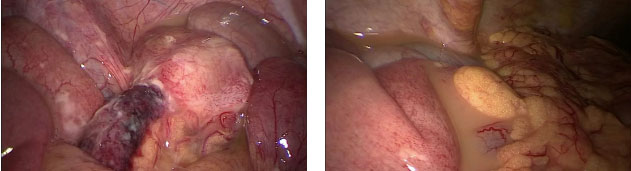

患者阑尾坏死、脓液渗出影像

手术过程中,外科副主任杨景能及团队凭借精湛的技艺,为患者实施了急诊腹腔镜探查+阑尾切除术+腹腔冲洗引流术。术中证实患者阑尾已坏疽穿孔,腹腔内大量脓性液渗出。团队精准、快速地为患者完成了阑尾切除,对腹腔脓液进行了彻底的清理冲洗。麻醉科医生全程密切监测患者的生命体征,确保手术顺利进行。